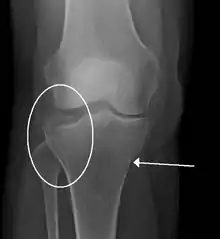

A tibial plateau fracture